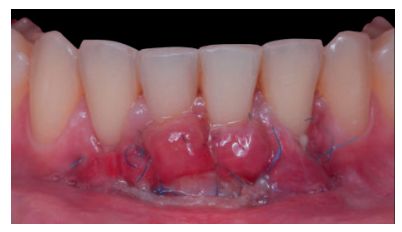

El examen clínico periodontal reveló la presencia de recesión gingival de 5 mm en el diente 31 con una profundidad de sondaje vestibular de 2 mm (perdida de inserción clínica de 7 mm). Presentaba inflamación gingival, además de un frenillo labial inferior insertado en el margen apical de la recesión gingival. El tejido queratinizado faltaba por completo a nivel del diente con recesión (Figura 1). Debido a que el defecto gingival se extendía más allá de la línea mucogingival, así como a la presencia de malposición dentaria, la recesión se categorizó como clase III de Miller6 y RT2 de Cairo7 .

Previamente a la intervención, la paciente se enjuagó durante 1 minuto con un colutorio de clorhexidina. La técnica quirúrgica comenzó con la preparación del lecho receptor, para ello se realizó una incisión sulcular a espesor parcial a nivel de la recesión, se continúo diseccionando apical y lateralmente, extendiéndose de 3 a 5 mm de la recesión para permitir la entrada del ITC y su estabilización. Posteriormente, se realizó una incisión en el fondo de vestíbulo, dejando un puente de tejido que servirá para un doble aporte sanguíneo al injerto (Figura 2).